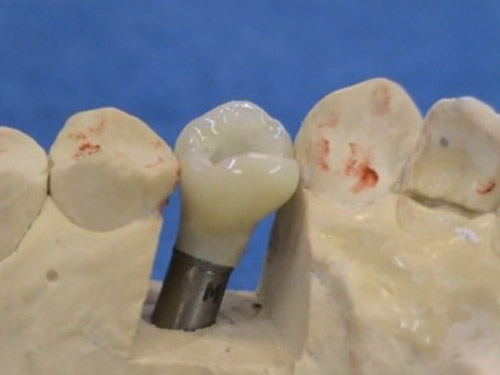

3. PHASE – prosthetic fabrication of temporary crown on implant

3. PHASE – fabrication of temporary solution